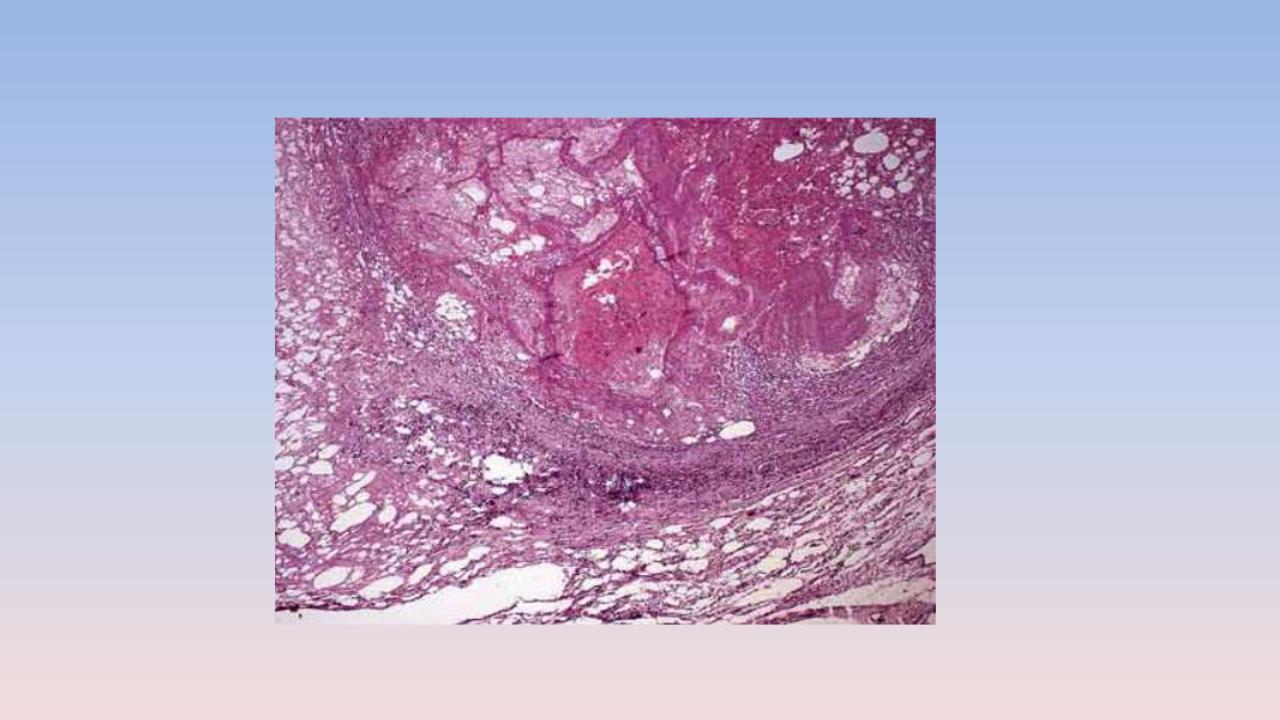

1. Смешанный тромб